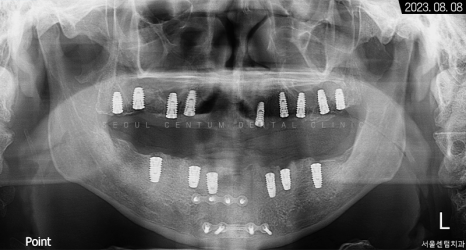

3개월이 더 지난 후 치근단 사진과 파노라마 엑스레이 사진으로 살펴봐도 초기 임플란트 식립 상황과 동일하게 견고히 자리 잡아 있는 것을 볼 수 있었습니다. 주위염도 생기지 않아 이상적인 결과를 만들어볼 수 있었어요.

그렇게 약 9개월의 전체임플란트 기간을 들여서 완성된 모습을 만날 수 있었는데요. 골융합을 높이기 위해 네오 브랜드와 폰틱을 결합하여 사용했습니다.

임플란트를 하면서 심미적으로 보완이 되었고 지르코니아를 수복함에 따라 깍두기, 나물, 고기처럼 질기거나 딱딱한 편의 음식을 예전보다 마음껏 드실 수 있게 되었습니다. 뼈 이식술도 동반했기에 픽스처가 더 힘을 잘 받을 수 있게 됐습니다.